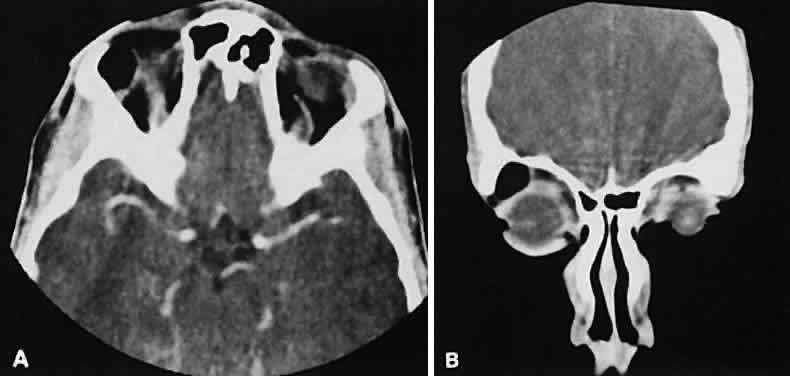

Malignant lesions of the lacrimal gland, conversely, often appear invasive, with bone destruction evident on the CT scan (Fig. 17). Intralesional calcium may be present.63,64 The use of contrast material facilitates detection of lesions that extend beyond the confines of the orbit.

Fig. 17. Adenocarcinoma of the lacrimal gland. A. Unenhanced axial view shows the speckled calcification of a lacrimal gland tumor. B. Contrast-enhanced view at about the same level shows intense enhancement and vascularity. In axial views at a higher level, an unenhanced scan (C) is unremarkable, although a contrast-enhanced view (D) at the same level highlights intracranial extension (arrows). E. Reconstructed coronal view has bone destruction with extension into the intracranial and temporalis fossae.